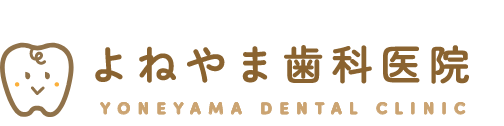

摂食嚥下障害とは、口から食べる機能の障害のことです。私たちは普段意識していませんが、食べ物を目や脳において認識して口まで運び、口の中に入れて噛み、ゴックンと飲み込むことで、食物から液体を摂取しています。これらの動作の1つまたは複数が、何らかの原因で正常に機能しなくなった状態を言います。 健康な成人の方であれば、誤って気管に入った場合も自然反射的に吐き出したり、細菌から身を守る免疫力が十分に備わっているので、大きな問題にはなりませんが、高齢者、 特に寝たきりや身体が不自由な方は、そうした自然反射的な動作が難しいので、細菌が気管に入りやすく、さらに抵抗力や免疫力の低下から、誤嚥性肺炎になりやすいと言われています。

摂食嚥下障害とは、どのような障害か

摂食嚥下障害とは、口から食べる機能の障害のことです。私たちは普段意識していませんが、食べ物を目や脳において認識して口まで運び、口の中に入れて噛み、ゴックンと飲み込むことで、食物から液体を摂取しています。これらの動作の1つまたは複数が、何らかの原因で正常に機能しなくなった状態を言います。 健康な成人の方であれば、誤って気管に入った場合も自然反射的に吐き出したり、細菌から身を守る免疫力が十分に備わっているので、大きな問題にはなりませんが、高齢者、 特に寝たきりや身体が不自由な方は、そうした自然反射的な動作が難しいので、細菌が気管に入りやすく、さらに抵抗力や免疫力の低下から、誤嚥性肺炎になりやすいと言われています。

2.誤嚥性肺炎

摂食嚥下障害とは、口から食べる機能の障害のことです。私たちは普段意識していませんが、食べ物を目や脳において認識して口まで運び、口の中に入れて噛み、ゴックンと飲み込むことで、食物から液体を摂取しています。これらの動作の1つまたは複数が、何らかの原因で正常に機能しなくなった状態を言います。 健康な成人の方であれば、誤って気管に入った場合も自然反射的に吐き出したり、細菌から身を守る免疫力が十分に備わっているので、大きな問題にはなりませんが、高齢者、 特に寝たきりや身体が不自由な方は、そうした自然反射的な動作が難しいので、細菌が気管に入りやすく、さらに抵抗力や免疫力の低下から、誤嚥性肺炎になりやすいと言われています。